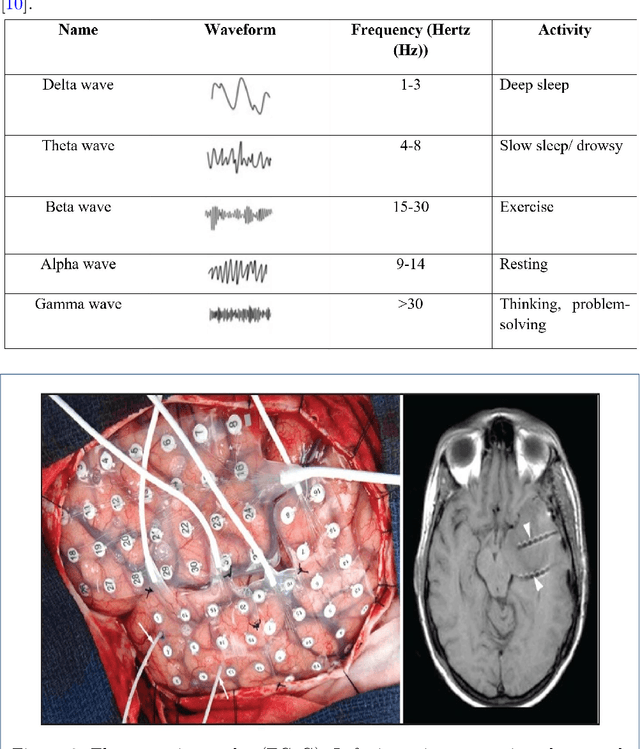

Abstract:Brain signals constitute the information that are processed by millions of brain neurons (nerve cells and brain cells). These brain signals can be recorded and analyzed using various of non-invasive techniques such as the Electroencephalograph (EEG), Magneto-encephalograph (MEG) as well as brain-imaging techniques such as Magnetic Resonance Imaging (MRI), Computed Tomography (CT) and others, which will be discussed briefly in this paper. This paper discusses about the currently emerging techniques such as the usage of different Deep Learning (DL) algorithms for the analysis of these brain signals and how these algorithms will be helpful in determining the neurological status of a person by applying the signal decoding strategy.